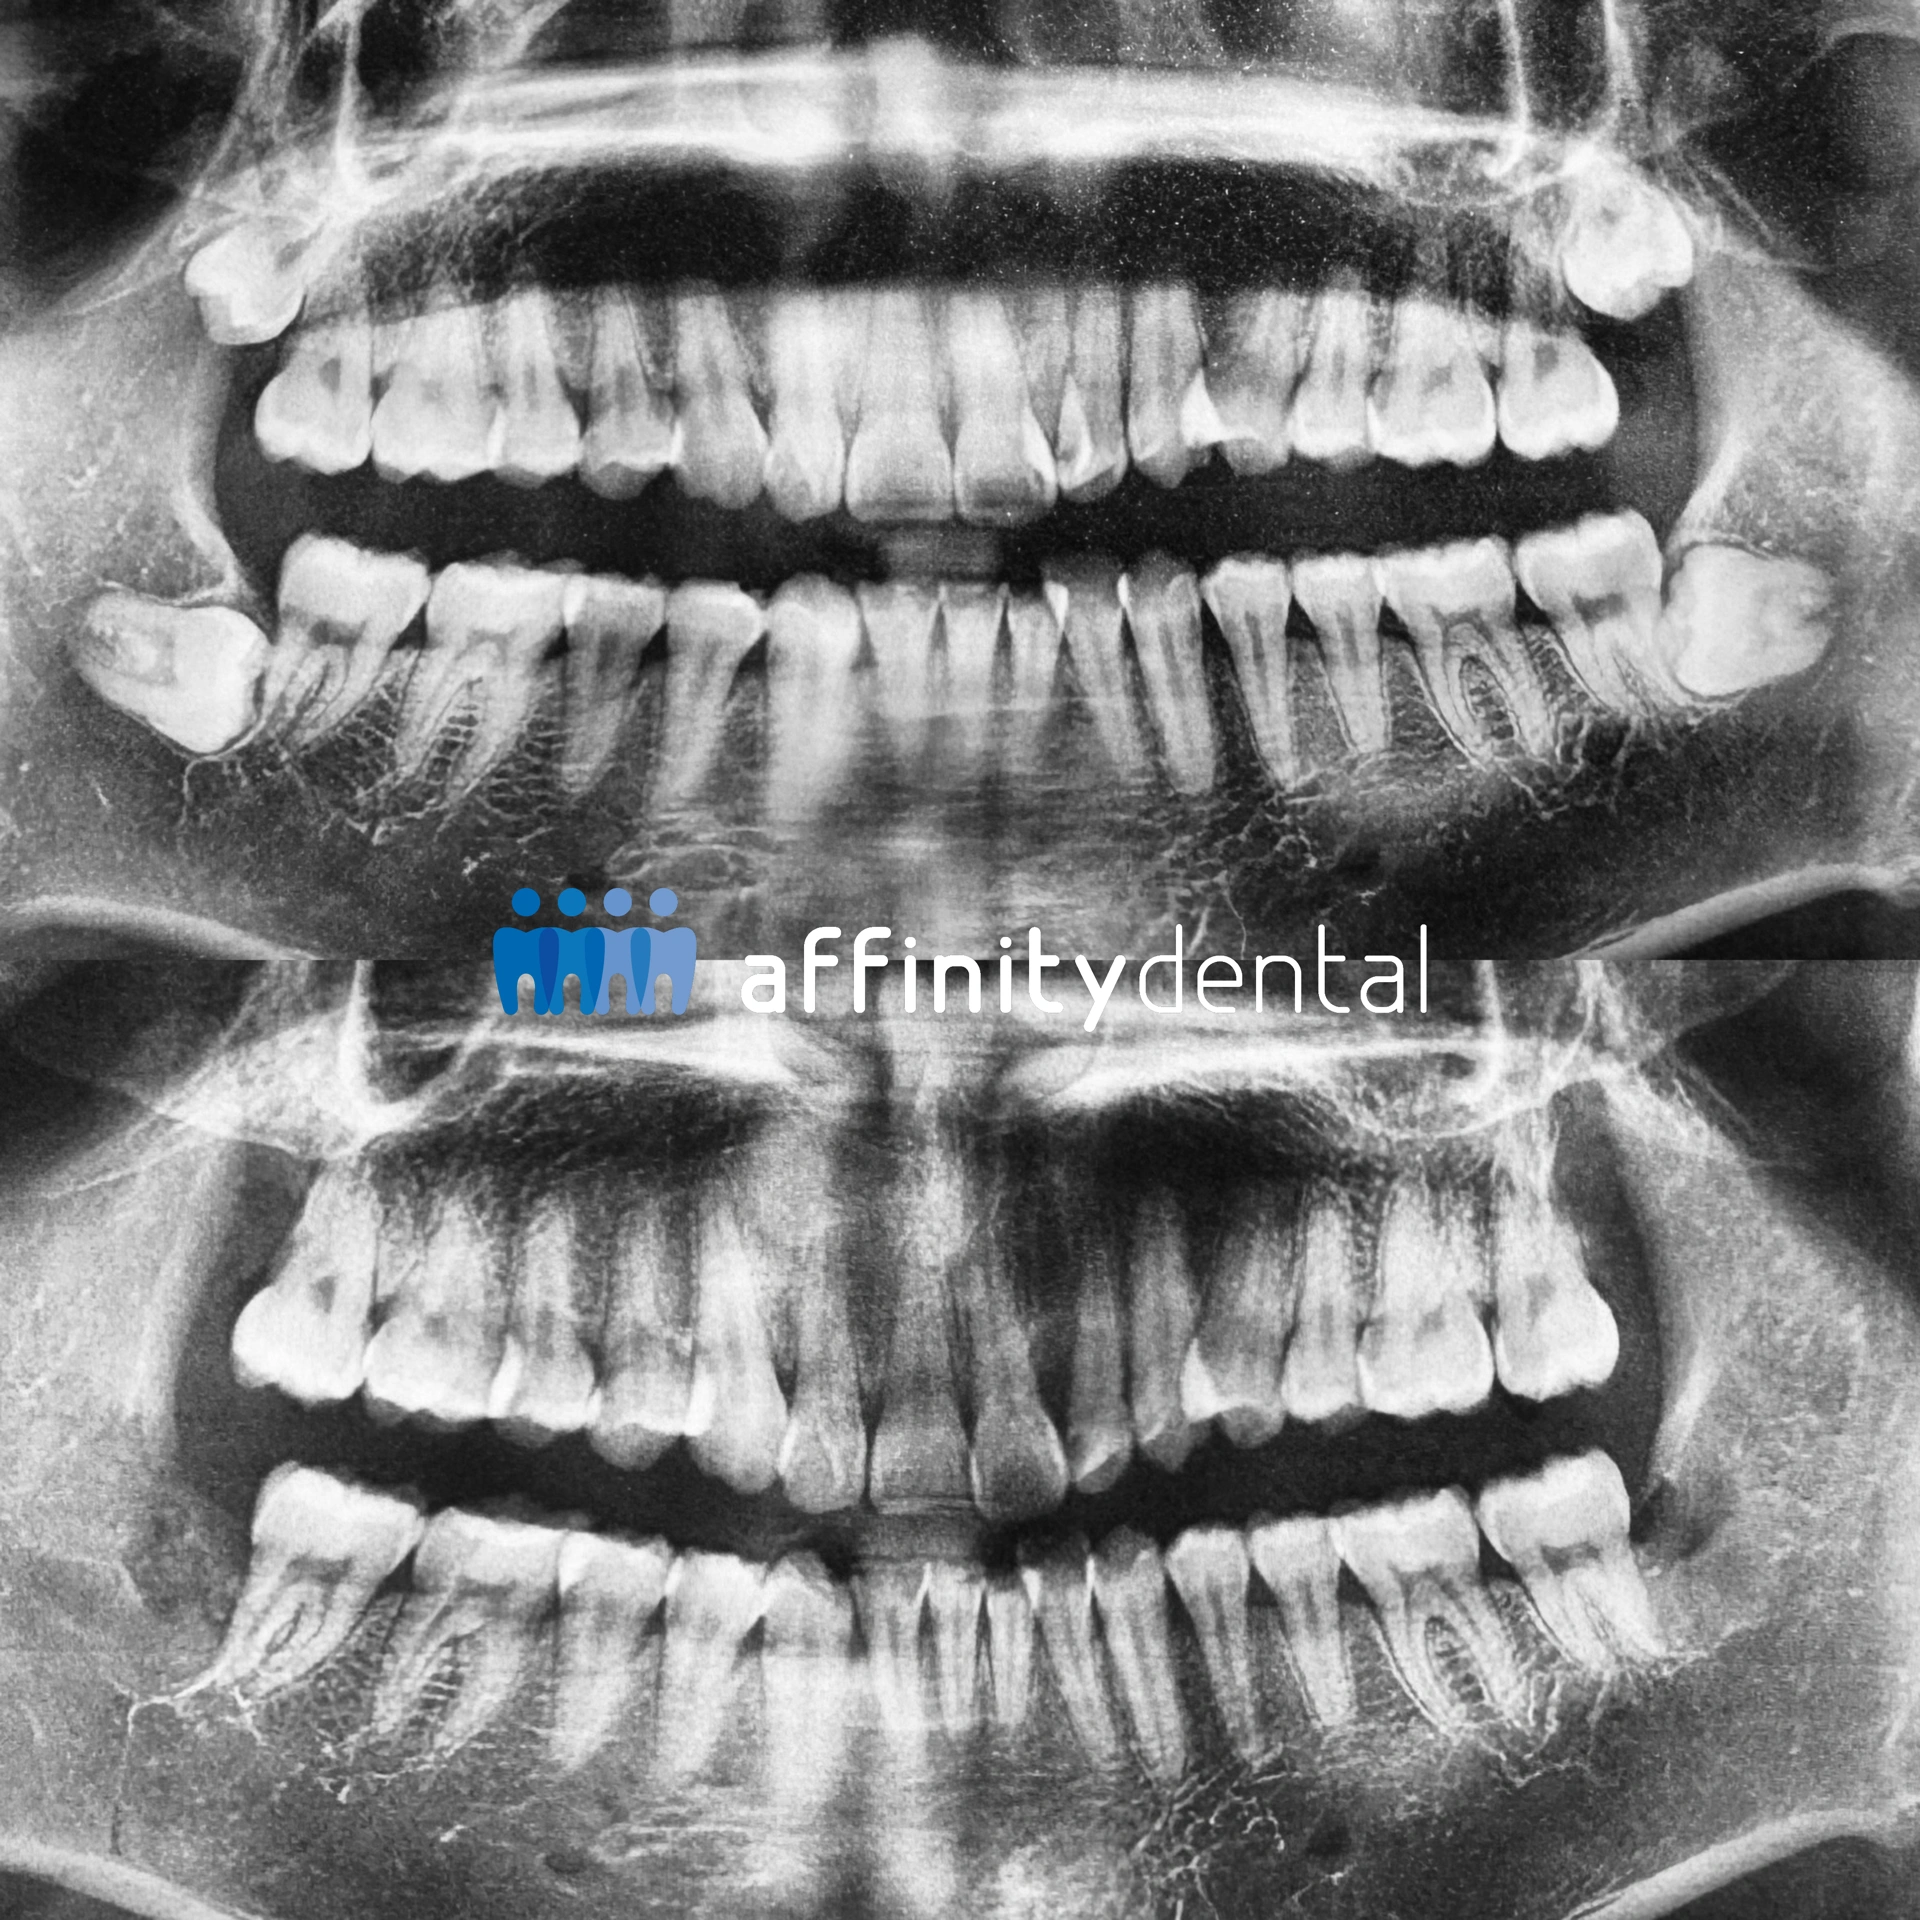

An educational poster illustrating the six main types of wisdom tooth impaction that can cause pain, infection, or crowding.

The best step? Have your dentist examine the tooth, take an X-ray, and discuss your options. At Affinity Dental Clinics, we use digital X-rays and CBCT scans (when needed) to clearly see the position of your wisdom teeth before making any recommendation.